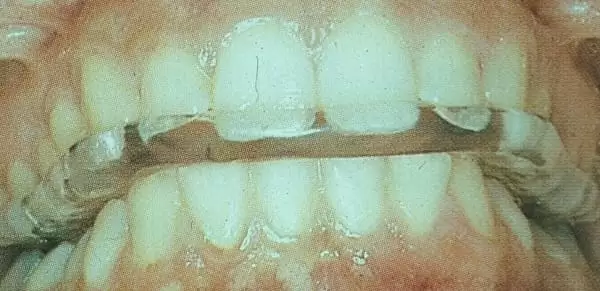

圖說:以"顳顎關節咬合板"治療顳顎關節疼痛